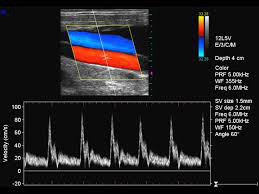

L'examen doppler a essentiellement pour but d'étudier la circulation des globules rouges dans les vaisseaux (artères ou veines). Le doppler n'utilise pas les rayons X et, en principe, l'examen Doppler ne nécessite pas d'injection de produit de contraste. Le Doppler est donc une technique d'étude des vaisseaux qui est non-invasive.

La formation des images en Doppler comme en échographie repose sur les propriétés des ondes sonores réfléchies par les différentes structures étudiées. Un faisceau d'ondes sonores est émis par une sonde d'échographie. Lorsque le faisceau frappe une structure en mouvement, les ondes sonores réfléchies ont une fréquence différente. Cette fréquence sera augmentée si la structure en mouvement se dirige vers la sonde d'échographie; elle sera diminuée si la structure en mouvement s'éloigne de cette sonde. Les informations recueillies lors d'un examen Doppler sont basées sur les différences de fréquences entre l'onde sonore émise et l'onde sonore réfléchie.

Le doppler permet d'étudier tout aussi bien le flux dans les artères que les veines que ce soit dans l'abdomen, le cou ou les membres. Naturellement, le calibre du vaisseau a une influence sur la fiabilité de l'étude doppler: plus ce calibre est petit, plus l'étude devient compliquée et par conséquent moins fiable. Plus les vaisseaux étudiés sont localisée profondément dans le corps, plus l'étude Doppler peut devenir difficile.